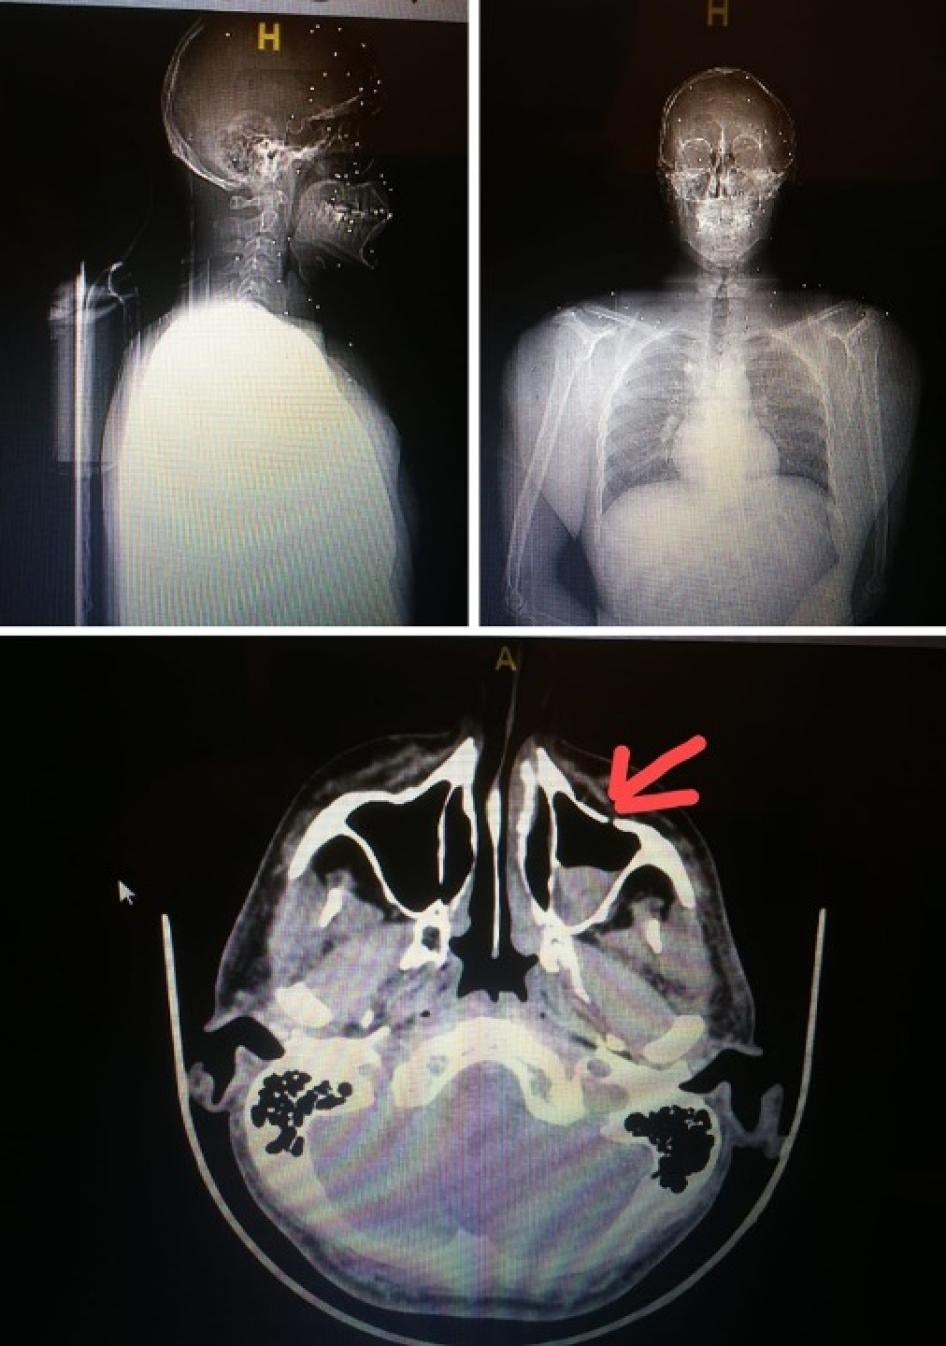

Elie Saliba was hit with metal pellets. On the right, an x-ray shows a metal pellet that had embedded in his head. © 2020 Courtesy of Elie Saliba

Elie Saliba, a doctor who attended the protest, said that at around 5:15 p.m., security forces fired metal pellets from a pump-action weapon at him when he was between the former Virgin Megastore and the UFA Assurances Building near Martyrs’ Square. A metal pellet hit his shoulder. He then went to the roof of the Virgin Megastore building to film the security forces, including men in civilian clothes and soldiers, but he was shot at with metal pellets again, from a distance of about 20 meters. Although he was wearing a helmet, three metal pellets embedded in his head. He removed two on the spot. The next day, doctors removed the third one.